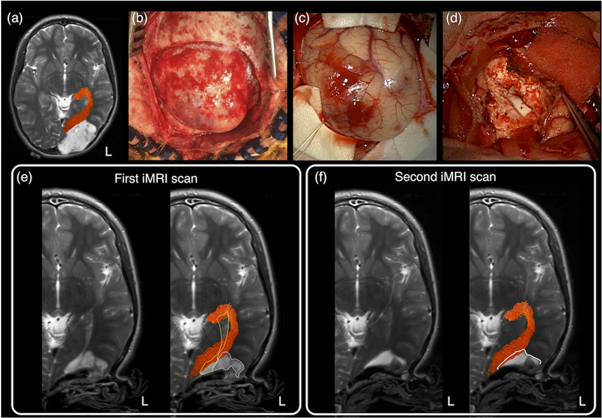

In a recent survey conducted from 36 out of all 40 neurosurgical units in the UK and Ireland, 90% of the neurosurgical units use tractography regularly, and they are predominantly DTI-based reconstructions. Concerningly, many neurosurgeons remain unfamiliar with the underlying methods used to produce tractography visualisations (Toescu et al 2020). An alternative way to provide a snapshot of clinical practice is to look at relevant tractography surgical cohort reporting. An author-initiated PudMed-based search for relevant literature over the last 25 years, demonstrating the striking contrast between the advanced dMRI-informed tractography research and what is being utilised and published from the clinical neurosurgical practice. Overwhelmingly, 94.7% of neurosurgical publications utilised DTI-based tractography, with the remaining 5.3% of studies utilised higher-order dMRI modelling techniques. Importantly, although many of these studies recognised the limitation of DTI-based tractography, and emphasised the need to introduce more advanced methods, none had actually proceeded with furthering research and industry partnership, working towards translating advanced dMRI methodologies into neurosurgical practice (Kuhnt et al 2012, Bucci et al 2013, Farquharson et al 2013, Kuhnt et al 2013, Zhang et al 2013, Lim et al 2015, Mormina et al 2015, Ashmore et al 2020, Fekonja et al 2021). Figure 10 shows a clinical example of differences in tractography appearances based on the selected dMRI modelling and tracking techniques.

Figure 10. A clinical case example showing tractography reconstruction using a combination of different modelling techniques and tracking algorithms and the impact on pre-surgical planning and intraoperative image-guidance. This is an 11- year-old girl presented with early clinical features suggestive of raised intracranial pressure, referable to a large left parieto-occipital high-grade glioma (glioblastoma multiforme). The corticospinal tracts (in blue), and optic radiations (in orange), and the brain tumour segmentation (in brown) are shown. The dashed white lines are the approximate image planes for the axial and coronal MR images, which are displayed in radiological convention. Note both the deterministic and probabilistic DTI tractography (Det_DTI and Prob_DTI) lead to the impression of gaps observed between the tumour margins and both white matter tracts; and failure to reconstruct the lateral projections of the corticospinal tract (i.e. the 'too-few', false-negative tracking problem). The use of the probabilistic tracking algorithm only partially recovers some of the 'missing' lateral corticospinal tract fibres. Using these tractography images in surgery can lead to inadvertent surgical injuries to both fibre tracts and associated functional consequences. On the other hand, reconstructions using a probabilistic fibre orientation distribution based (FOD) technique (Prob_FOD), combined with carefully placed regions-of-interest based on anatomical priors, limit the 'too-many', false-positive tracking problem. The reconstructed fibre tracts are anatomically more plausible in their appearances and are abutting the tumour margins—a critical piece of information for surgical approach and resection of this tumour. Material acronyms: Det_DTI (deterministic tracking algorithm, diffusion tensor imaging model), Prob_FOD (probabilistic tracking algorithm, fibre orientation distribution based), Prob_DTI (probabilistic tracking algorithm, diffusion tensor imaging), L (left).

Download figure:

Standard image High-resolution imageNonetheless, there remains a pressing need to bridge the evidence-practice gap between dMRI-informed tractography research on the one hand and clinical neurosurgery practice on the other. Establishing close clinical, research, and industry partnerships are key to further translate these novel techniques into the clinical neurosurgery realm (more to this in Q&A 8).